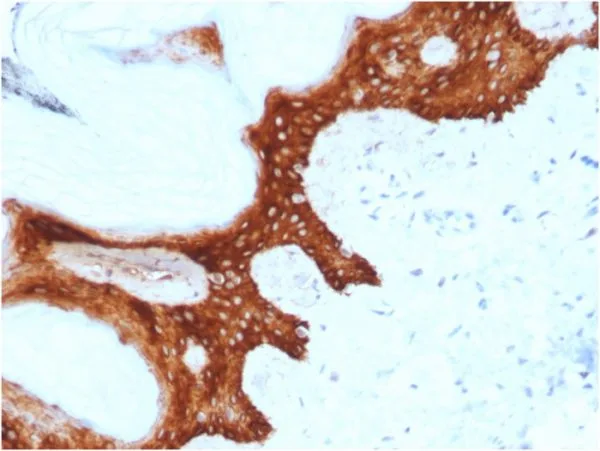

Immunohistochemistry (IHC) is a powerful technique for visualizing specific proteins in tissue sections, providing valuable insights for research and diagnostics. NeoBiotechnologies uses formalin-fixed, paraffin-embedded (FFPE) tissue samples to validate suitability of its antibodies for use in IHC applications.

Tissue microarrays (TMAs) are an efficient and powerful tool for validating antibodies for immunohistochemistry, immunofluorescence, and other applications, helping to ensure specificity and rule out cross-reactivity. TMAs allow for rapid screening of sensitivity and specificity, systematic testing of off-target binding, and quantitative scoring compared to expected staining patterns. NeoBiotechnologies regularly employs tissue microarrays as part of its validation process.